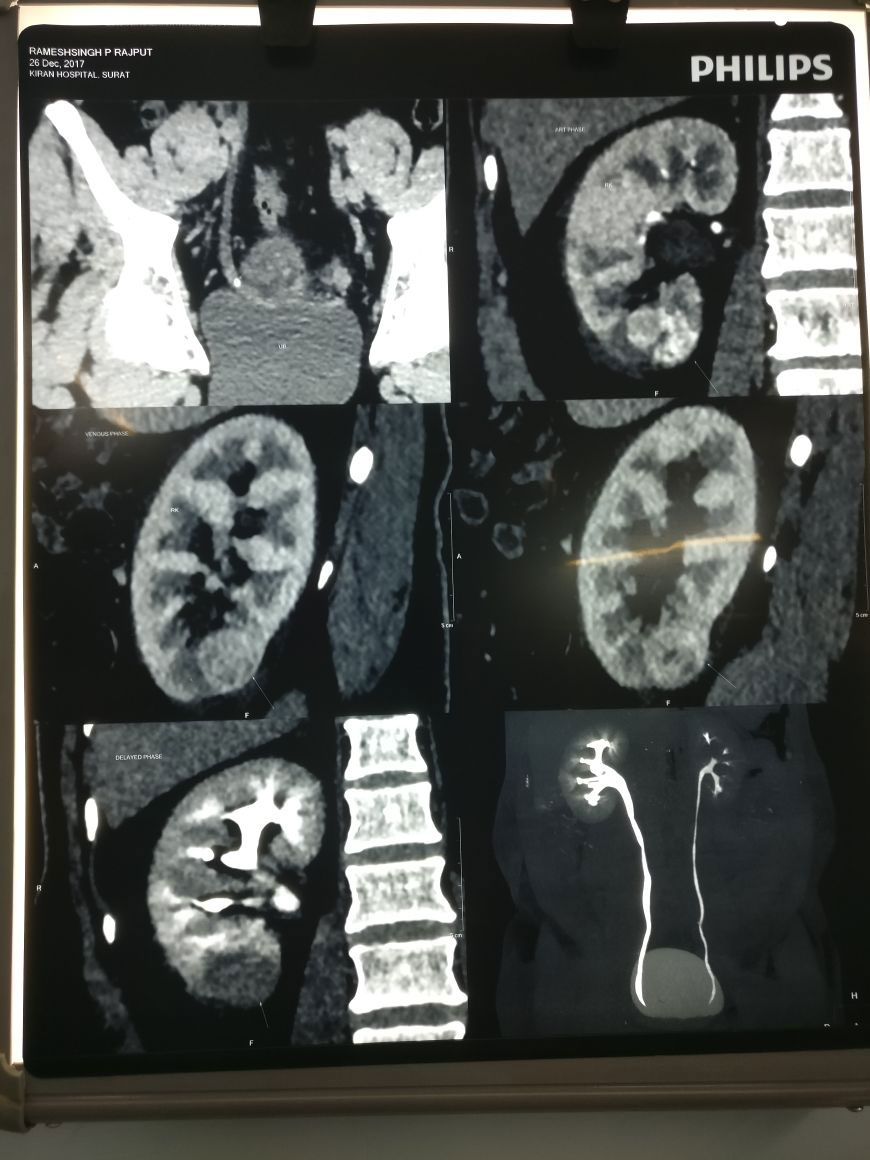

गुर्दे का कैंसर पहुंचा हार्ट तक, 8 घंटे की सफल सर्जरी के बाद स्थापित किया कीर्तिमान

Radical Nephrectomy